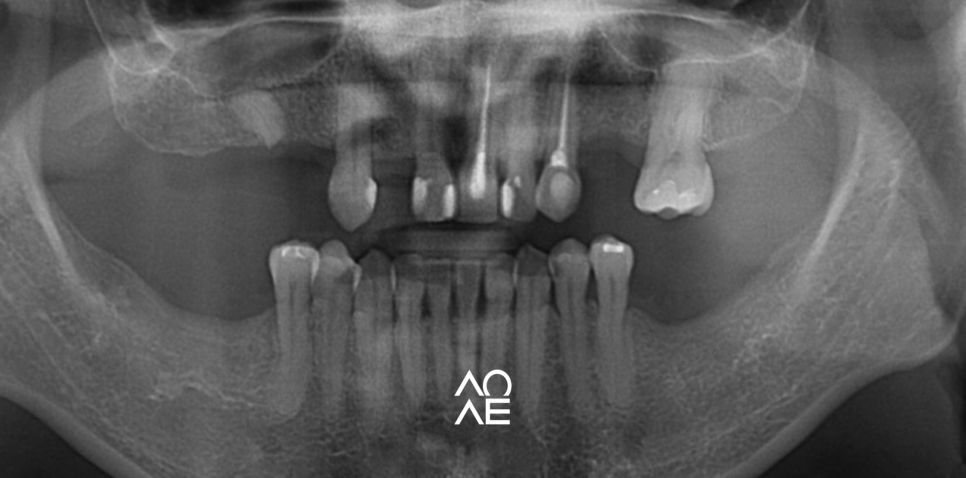

위 파노라마를 보시면, 환자분은

많은 치아가 상실되셨죠?

그런데, 어쨌든 위 / 또는 아래에

남아있는 치아가 있습니다.

이 경우에는 분류상으로 보면

무치악 환자는 아닙니다.

그래서, 위 또는 아래에 아무곳이나

선택을 하셔서 건강보험 임플란트를

받으실 수 있는 케이스 입니다

(위, 아래 모두 가능)